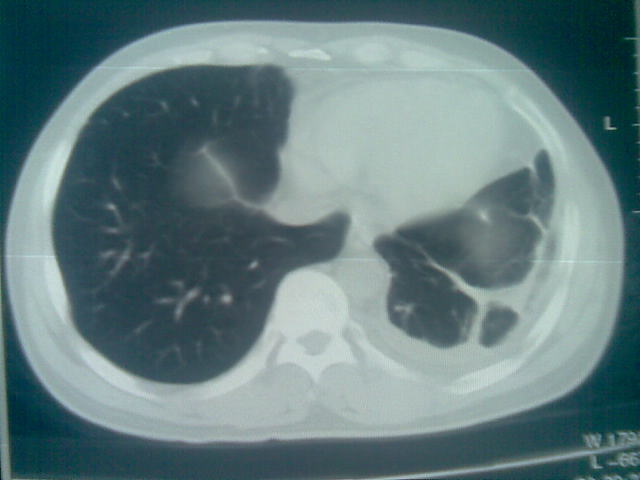

标题: CT23981:男,38岁阑尾炎术后透视胸腔积夜!做CT如下!积液包 [打印本页]

标题: CT23981:男,38岁阑尾炎术后透视胸腔积夜!做CT如下!积液包

.胸膜增厚粘连见少量气体。包裹脓气胸

左侧胸膜增厚、粘连+包裹液气胸。